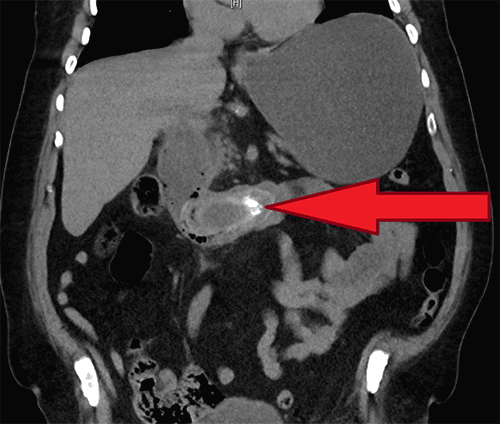

Figure 1. Coronal CT Demonstrating Impacted Duodenal Gallstone and Associated Pneumatosis. Published with Permission

Non-contrast coronal CT of the abdomen. The image shows a large, ovoid intraluminal filling defect (arrowhead), consistent with the impacted 8.3 cm gallstone, within the second and third portions of the duodenum, associated with surrounding pneumatosis intestinalis

Upon initial evaluation, vital signs were: heart rate 108 beats/minute, blood pressure 123/74 mmHg, respiratory rate 18 breaths/minute, oxygen saturation 97% on 2 liters/minute supplemental oxygen via nasal cannula, and temperature 36.8°C (98.3°F). Pertinent laboratory findings included hypokalemia (3.1 mmol/L), hypochloremia (87 mmol/L), and acute kidney injury with creatinine of 2.97 mg/dL. Liver function tests showed a total bilirubin of 0.7 mg/dL and an alkaline phosphatase of 116 U/L. Sepsis workup revealed a markedly elevated lactate of 13.1 mmol/L and significant leukocytosis (17,800/uL). Physical examination demonstrated moderate abdominal distension with mild epigastric tenderness, without rebound tenderness or guarding. A non-contrast computed tomography (CT) scan of the abdomen and pelvis revealed significant gastric distension with copious intraluminal fluid, an ovoid foreign body measuring 8.3 cm × 3.7 cm × 3.6 cm impacted between the second and third portions of the duodenum, associated with surrounding duodenal pneumatosis (Figure 1). Pneumobilia was also evident (Figure 2). Following aggressive intravenous fluid resuscitation for acute renal failure and lactic acidosis, a nasogastric tube was inserted, yielding an immediate return of three liters of dark gastric fluid. His anticoagulation was reversed with prothrombin complex concentrate, and empiric broad-spectrum antimicrobial therapy with intravenous fluconazole 400 mg and piperacillin-tazobactam 2.25 g was administered. The patient was subsequently transferred to our tertiary care center for urgent hepato-pancreato-biliary surgical consultation.